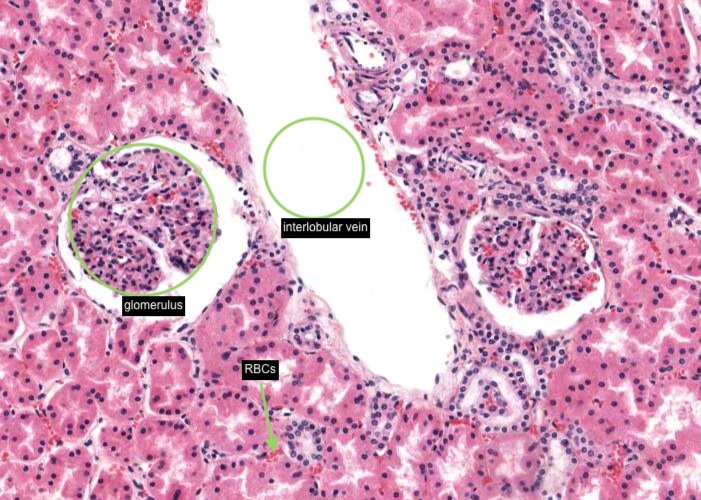

A renal corpuscle is located in the cortex and is the specialised structure where filtration occurs. Each is an aggregation of capillaries enclosed within a cup-shaped capsule called the glomerular (Bowman’s) capsule. Identify red blood cells within these capillaries. The capsule has an outer (parietal) surface layer of squamous epithelial cells and the inner (visceral) layer invests the glomerular capillaries.

The space between the glomerular capillaries and the parietal layer of Bowman’s capsule is referred to as the capsular or urinary space. This space receives plasma fluid that filters through the glomerular capillaries and the visceral layer of epithelial cells called podocytes.

Interlobular arteries give off tiny afferent arterioles which run into the lobule to supply each renal corpuscle. An afferent arteriole enters a renal corpuscle, breaks up into a tuft of capillaries called a glomerulus, and then collects back into an efferent arteriole instead of a vein. This occurs at the "vascular pole". This is a nice image because it also shows part of a glomerulus with the urinary (tubular) pole visible (see more details in the next item). You may see an arteriole, but it will be impossible to tell whether it is afferent or efferent (although there is a slight hint that it is an afferent arteriole because it is adjacent to a distal convoluted tubule - ignore this though for now!). The efferent arteriole runs for only a short distance before breaking up into a second bed of peritubular capillaries, which nourish the proximal and distal tubules and absorb fluid. Even when these capillaries are collapsed you can easily see abundant red blood cells within their lumens between the convoluted tubules.

In the middle of each renal lobule are descending and ascending limbs of the nephron and a collecting duct. Collections of straight tubules and collecting ducts form the medullary ray within the cortex. The renal lobule is a cortical structure and nephrons in the same lobule drain into the collecting duct. Each interlobular artery branches into a number of afferent arterioles which each form a glomerulus, a capillary network and the efferent arteriole.

Firstly, the portion of the cortex contained within two adjacent interlobular arteries. e.g. interlobular artery (X) and (Y).

Secondly, it consists of a single collecting duct and the nephrons that drain into it. A medullary ray (Z) forms the axis of a renal lobule.

Tiny peritubular capillaries (you can see red blood cells within their lumens) are a continuation of the efferent arteriole exiting the glomerulus in the upper and middle cortex and are associated with tubules within the cortical labyrinth. Peritubular capillaries empty into an interlobular vein. In contrast, efferent arterioles exiting juxtamedullary glomeruli gives rise to vasa recta in the medulla.